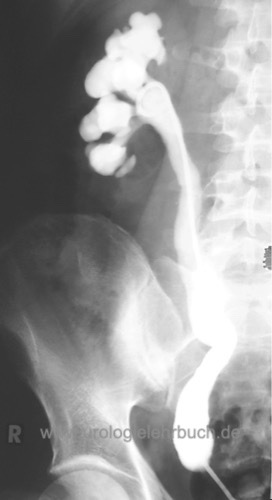

Retrograde Pyelographie:

Die retrograde Pyelographie wird zur Darstellung der Anatomie und zur Differentialdiagnose bei unklarer Bildgebung verwendet [Abb. 2.6], insbesondere bei verzögerter Diagnose im Erwachsenenalter.